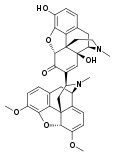

Opium alkaloids and derivatives

Phenanthrenes naturally occurring in (opium):

Preparations of mixed opium alkaloids, including papaveretum, are still occasionally used.